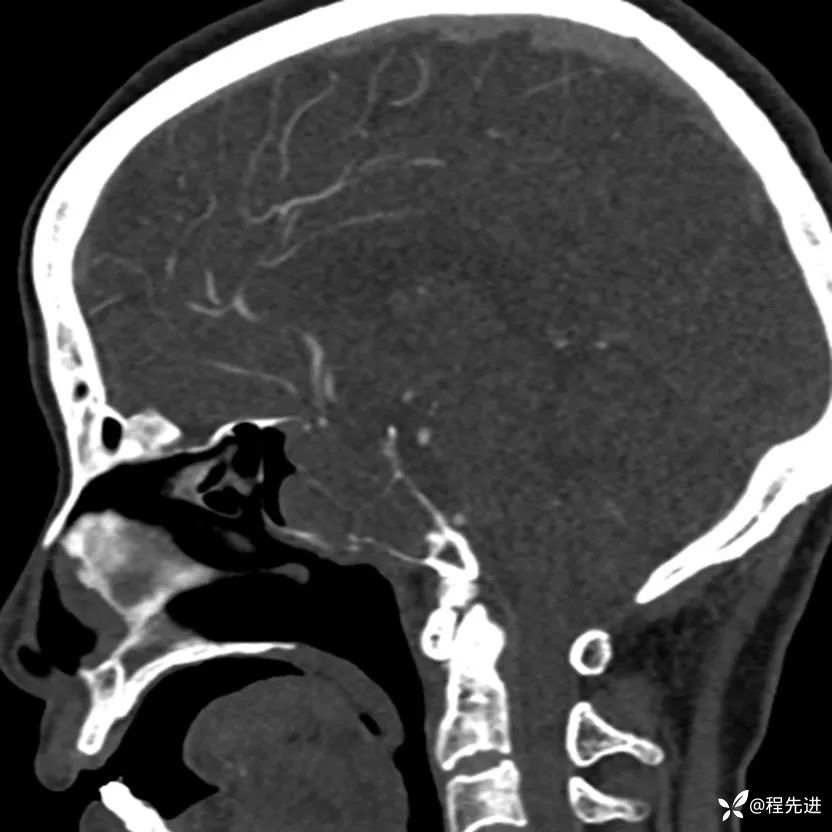

简要病史:外伤检查发现颅底占位

CT增强: